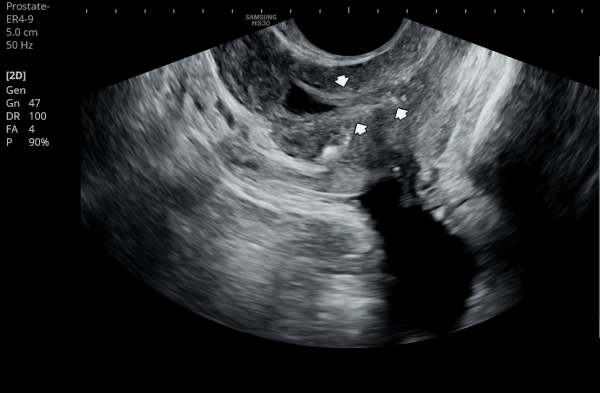

내원 첫 당일 경직장 전립선 초음파 검사상 사정관 입구의 결석들과 사정관 낭종이 관찰되는 사진입니다.(NIH:24)

On the initial transrectal prostate ultrasound, the image shows the presence of calcifications (stones) at the opening of the ejaculatory duct as well as a cystic lesion within the ejaculatory duct (ejaculatory duct cyst).(NIH:24)

주 2회 14주 동안 전립선과 정낭, 사정관과 정관등의 표적 치료후 사정관의 낭종등이 치료 되고 있는 경직장 전립선 초음파 검사 자료 입니다.(NIH:13)

This transrectal prostate ultrasound image shows improvement of an ejaculatory duct cyst after targeted treatment of the prostate, seminal vesicles, ejaculatory ducts, and vas deferens.

The treatment was performed twice a week over a period of 14 weeks. As a result, the previously noted cyst in the ejaculatory duct is gradually resolving, indicating improved drainage and recovery of normal ductal circulation.(NIH:13)

For the patient, this means that small stones and a cyst are blocking the natural passage where semen normally flows. These findings can explain symptoms such as pelvic pain, difficulty with ejaculation, blood in semen, or infertility.

Treatment may involve addressing these blockages to restore normal flow and relieve associated symptoms.